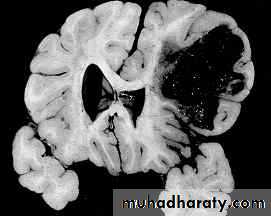

4. Cortical Lacerations

It is due to rapid movement and shearing of brain tissue.

The pia arachnoid is torn, with bloody effusion in the CSF.

Intracerebral haemorrhage may accompany this lesion.

Focal deficits are the rule.